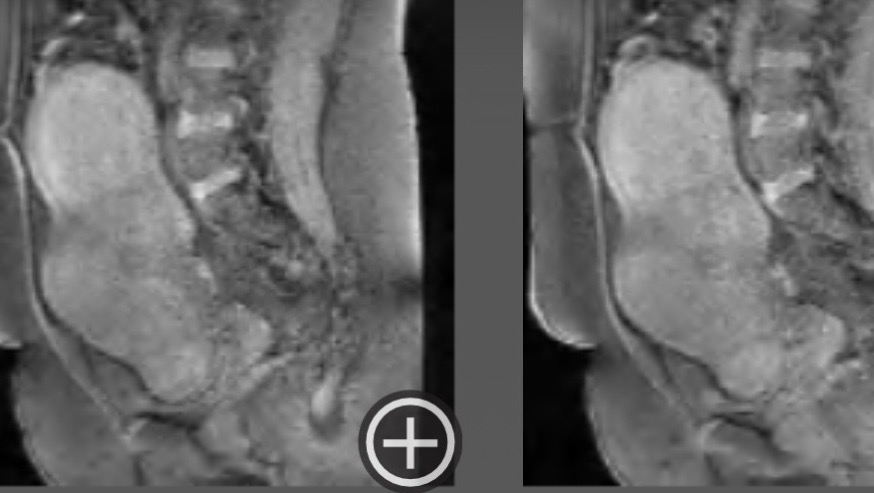

On November 10th, 2025, I was scheduled with an OBGYN who finally gave me a proper diagnosis and confirmed that I’ve been living with Uterine Fibroids. Confirming that doctors & specialists have been dismissing my symptoms and clear family history for years.

Uterine Fibroids are noncancerous growths of the uterus that are extremely common for Black women. Unfortunately, my pelvic sonogram showed a markedly enlarged uterus with 5 medium-sized fibroids and other smaller fibroids. (doctor informed me there’s 30+.) To give you an example of the sizes of my fibroids, they all vary between as small as a strawberry and as large as a grapefruit or small watermelon.

My doctors communicated that these fibroids have been living in me for roughly 9-10 years, and that one of my fibroids is the size of a 7-month-old child. So for that long, doctors throughout the years continued to ignore my symptoms and family history to the point where I managed to normalize and cope with the pain and symptoms I’ve felt. Knowing I’m about to feel like an entirely different person once they’re all removed has been very overwhelming. Please be patient with me. Thank you for reading and sharing. I genuinely appreciate all of your support, xo.